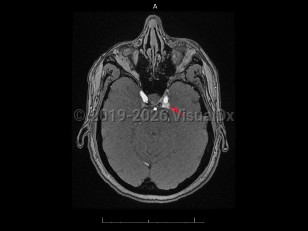

Carotid-cavernous fistula

Acquired vascular abnormality involving communication between the cavernous sinus and the carotid artery or branches. It may arise spontaneously or through injury by blunt head trauma, surgery, or vascular and connective tissue disorders, or following cavernous carotid aneurysm rupture. Onset may be delayed. Carotid-cavernous fistula (CCF) are classified as high-flow (direct) or low-flow (indirect), depending on the pressure and direction of the communicating arterial blood flow. Common symptoms include bruit, proptosis, diplopia, blurred vision, visual loss, conjunctival injection, eye pain, headache, and chemosis. CCF affects men and women about equally. Rarely, they appear bilaterally.

Treatment depends on the classification of the CCF, with endovascular obliteration being the first approach to closure, although multiple procedures may be necessary.